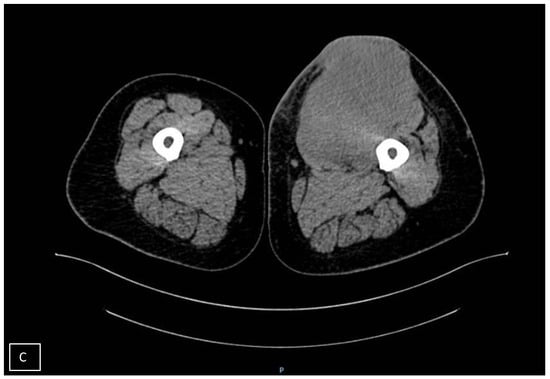

- Spinnato, P.; Clinca, R.; Vara, G.; Cesari, M.; Ponti, F.; Facchini, G.; Longhi, A.; Donati, D.M.; Bianchi, G.; Sambri, A. MRI Features as Prognostic Factors in Myxofibrosarcoma: Proposal of MRI Grading System. Acad. Radiol. 2021, 28, 1524–1529. [Google Scholar] [CrossRef] [PubMed]